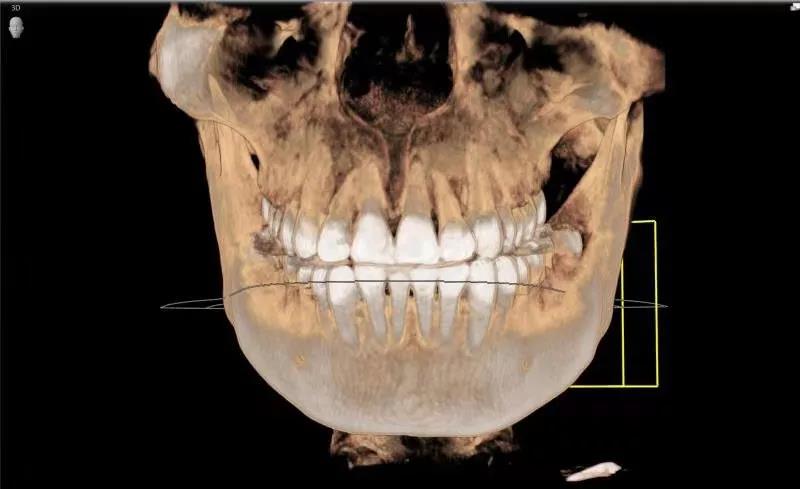

CBCT是曲面断层的升级版牙片,它将牙片从二维变成了三维,那它的优点有哪些呢?

①首先是高度还原口内硬组织情况,在三维角度更加清晰地显示牙齿、牙槽骨、上颌窦、下颌神经的位置及高度。医生可360度旋转查看口腔状况,不遗漏任何一个可能成为疾病的病灶。